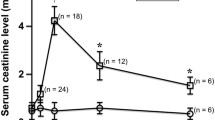

Renal histology showed severe tubular injury at d1 + d7 in both AKI groups, whereas, at d28, only animals with prolonged 45-min ischemia showed persistent signs of AKI. Following both AKI severities T1-values significantly increased and peaked at d7. T1-times in the contralateral kidney without AKI remained stable. At d7 relative T1-values in the outer stripe of the outer medulla were significantly higher after severe than after moderate AKI (138 ± 2 % vs. 121 ± 3 %, p = 0.001). T1-elevation persisted until d28 only after severe AKI. Already at d7 T1 in the outer stripe of the outer medulla correlated with kidney volume loss indicating CKD (r = 0.83).